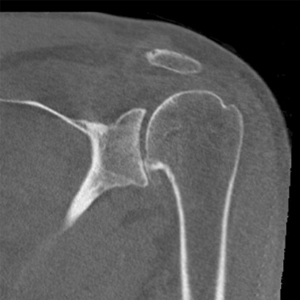

- Pyrocarbon hemiarthroplasty is a new option for patients (particularly younger, more active) with advanced arthritis

- Because a plastic socket is not placed into the socket, there is no risk of socket loosening with time

- While 10 year follow up from Europe demonstrates very low need for second surgery at 10 years (11%), an important factor is that the surgeon size the head correctly during surgery

Pyrocarbon shoulder hemiarthroplasty